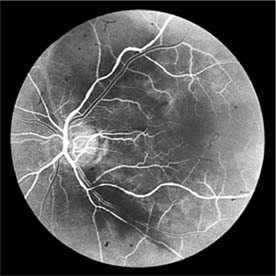

Figure 15-10

Figure 15-10: Accelerated hypertension. Fluorescein angiogram in a young man showing arteriolar constriction, dilation of capillaries with microaneurysms, and areas of closure. Marked disk edema is present.